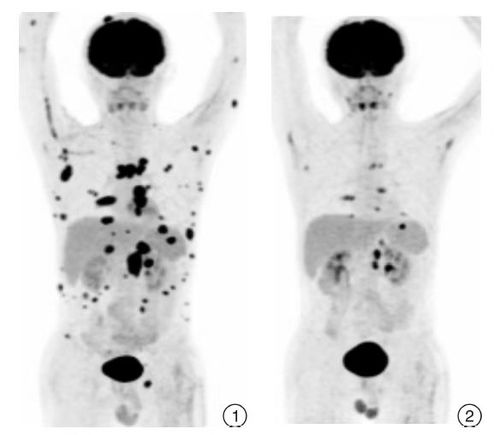

诊断是战斗的第一步。医生会通过影像学检查、血液检查、病理学检查等多种手段来确定肿瘤的类型、大小、位置等信息。治疗则包括手术、放疗、化疗、靶向治疗、免疫治疗等多种手段。